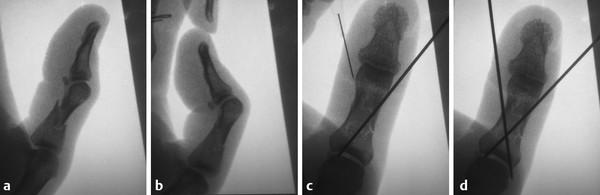

14.1 Jahss Maneuver

This is a useful technique to help manipulate the neck of fifth metacarpal fractures. It is also useful intraoperatively when fixing fifth metacarpal fractures. The fracture is reduced by flexing the metacarpophalangeal joint (MCPJ) and proximal interphalangeal joint (PIPJ) of the little finger to 90 degrees and using the proximal phalanx to push up the head of the fifth metacarpal thereby reducing it (Fig. 14‑1, Fig. 14‑2, Fig. 14‑3).